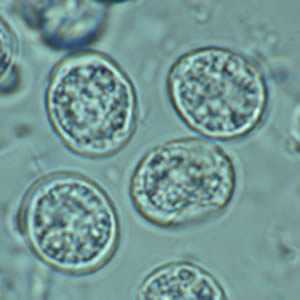

Toxoplasma gondii unsporulated oocysts.

Figure A: Unsporulated T. gondii oocyst in an unstained wet mount.

Figure B: Unsporulated oocyst of T. gondii in an unstained wet mount, viewed with differential interference contrast (DIC) microscopy.

Figure C: T. gondii oocysts in a fecal floatation.

Figure D: Higher magnification of Figure C.